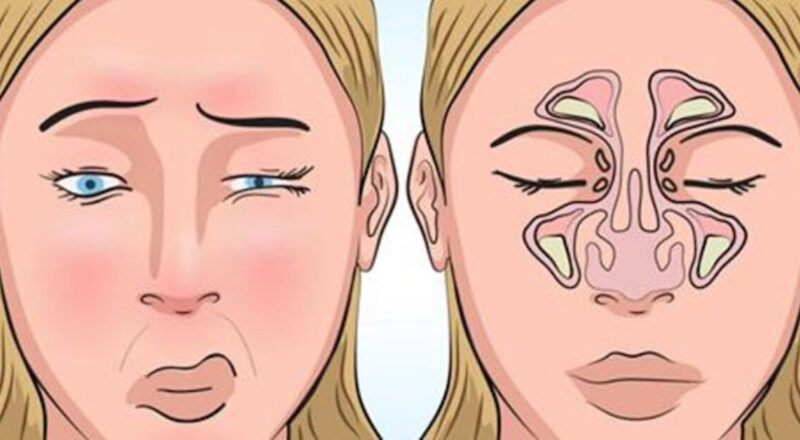

Continue lendoAdeus, rinite e sinusite! Você vai limpar totalmente o nariz e os seios paranasais com este tratamento caseiro

A sinusite é causada pela inflamação da membrana que reveste as cavidades ósseas que estão em contato direto com o nariz. Geralmente, a sinusite ocorre […]